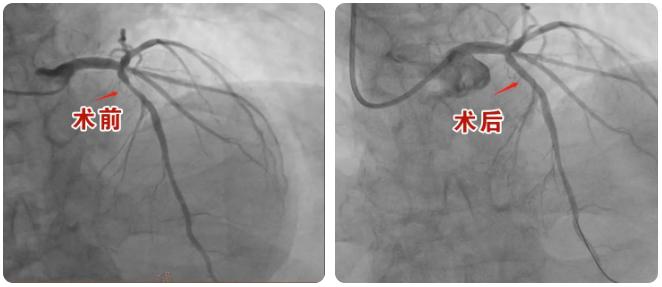

42岁的患者朱先生,因“发作性胸痛2个月,加重2天”到心血管内二科就诊,入院后诊断为不稳定型心绞痛,造影检查显示前降支近段斑块浸润,局部70%左右狭窄。为准确评估冠脉病变、指导下一步治疗,昌乐县人民医院心血管内二科主任孟祥江建议患者行血管内超声(IVUS)检查,明确其血管病变处最小管腔面积仅2.32mm?、斑块负荷80%,狭窄程度70%-80%,已经达到冠脉支架植入标准,遂予以冠状动脉腔内成形术及冠状动脉药物涂层支架植入术,借助血管内超声精准“导航”,犹如具有“火眼金睛”,将血管内病变“看得”更直观、仔细。术后再次应用血管内超声(IVUS)检查,对冠脉病变情况及治疗后评估,显示支架贴壁良好,无夹层及血栓征象,达到预期手术效果。

2023年以来,心血管内二科开展血管内超声技术指导下的冠心病介入诊疗,术前应用IVUS检查,准确评估冠脉病变情况,术后应用IVUS检查评估支架贴壁情况、有无夹层及血栓征象,患者胸痛症状均改善、恢复良好,得到患者及家属的一致好评。进一步提升了医院在心血管疾病循证化、精准化、个体化治疗水平,更好地为广大心血管疾病患者提供更优质的精准医疗服务。